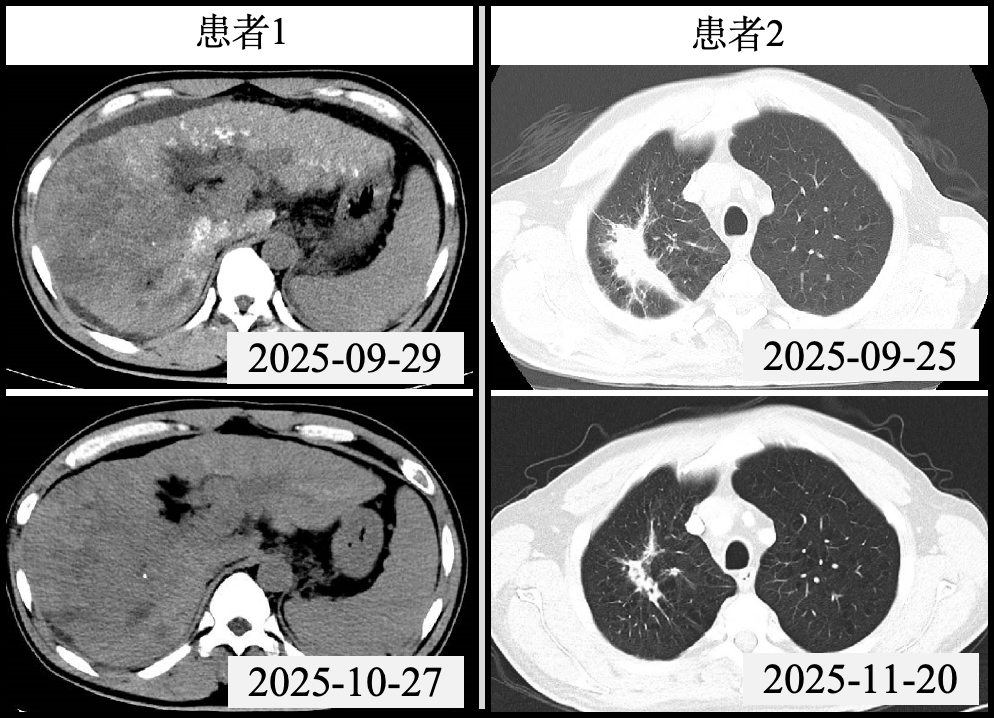

案例一:肝癌伴广泛门脉癌栓的序贯一体化治疗

50岁的于某被确诊为“巨块型肝癌”,影像学检查显示其原发性肝癌已伴随门静脉主干、左右支、部分肝内属支、脾静脉及肠系膜上静脉起始处广泛癌栓形成,病情极为棘手。面对这一复杂病例,肿瘤综合介入病区MDT团队迅速响应,第一时间敲定序贯一体化治疗方案。治疗初期,肿瘤综合介入病区副主任王田蔚与副主任医师金星带领介入团队为患者实施经动脉化疗栓塞术(TACE),有效控制了局部病情进展。

针对广泛门脉癌栓这一治疗关键难点,肿瘤放射治疗专家于多副教授带领放射免疫团队精准施策,为患者量身定制局部精准放疗联合分子靶向治疗的综合方案,通过放射免疫协同实现对病灶的立体管控。在多学科团队的精诚协作下,患者治疗过程顺利且耐受性良好,复查结果显示肿瘤及癌栓均得到有效抑制,患者生活质量显著改善。

案例二:肺癌伴椎骨转移的全流程一体化协作

61岁的姜某因肺癌骨转移入院,且已继发腰2椎体病理性骨折,随时面临瘫痪风险。同时,胸部CT检查显示其右肺上叶存在占位,伴有肺门及纵隔淋巴结转移,病情危急且涉及多系统问题,亟需同步解决病理诊断、脊柱稳定和肿瘤治疗三大核心任务。

肿瘤综合介入病区的一体化诊疗模式再次发挥关键作用。王田蔚率先为患者施行CT引导下经皮腰2椎体穿刺活检术,明确肿瘤为肺部来源后,立即实施经皮穿刺椎体成形术,成功重塑脊柱稳定性,为后续肿瘤治疗筑牢基础。

随后,于多领衔的放疗团队制定了“全身-局部”协同治疗策略:先通过诱导化疗控制全身微小病灶,再开展同步放化疗。放疗计划精准覆盖胸部原发肿瘤及高危淋巴结引流区,同时对腰椎转移灶进行局部加量照射,实现“全身控制”与“局部根治”的有机统一。目前,患者疼痛症状显著缓解,活动能力基本恢复,肺部及腰椎病灶明显缩小,治疗成效获得患者及家属的高度认可。